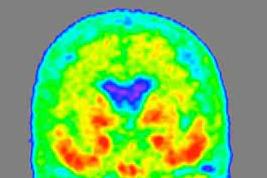

D.PET功能神经影像的特异性成像

■ 双侧颞、顶叶葡萄糖代谢率减低 。